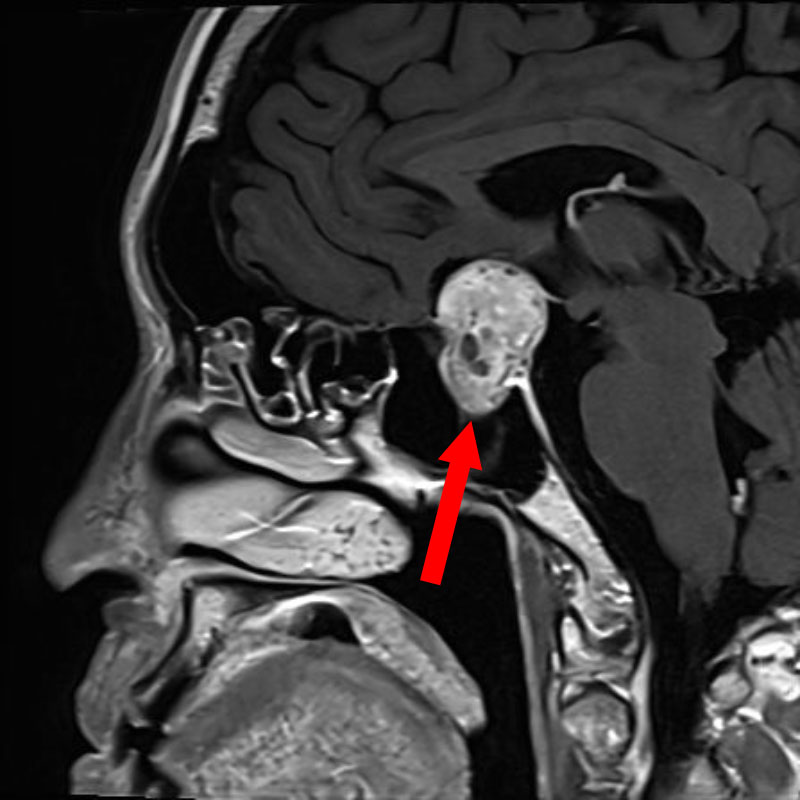

断層撮影

手術前1

手術前2